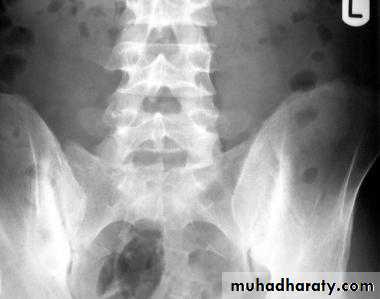

In chronic or recurrent disease, X-rays show joint space narrowing and proliferative erosions.Another characteristic feature is periostitis, especially of metatarsals, phalanges and pelvis, and large, ‘fluffy’ calcaneal spurs.

In contrast to AS, radiographic sacroiliitis is often asymmetrical and sometimes unilateral, and syndesmophytes are predominantly coarse and asymmetrical, often extending beyond the contours of the annulus (‘nonmarginal’)

Imaging of the axial skeleton often reveals features similar to those in chronic reactive arthritis, with coarse, asymmetrical, nonmarginal syndesmophytes and asymmetrical sacroiliitis.

Radiographic evidence of sacroiliitis is present in about 20–25% of IBD patients.